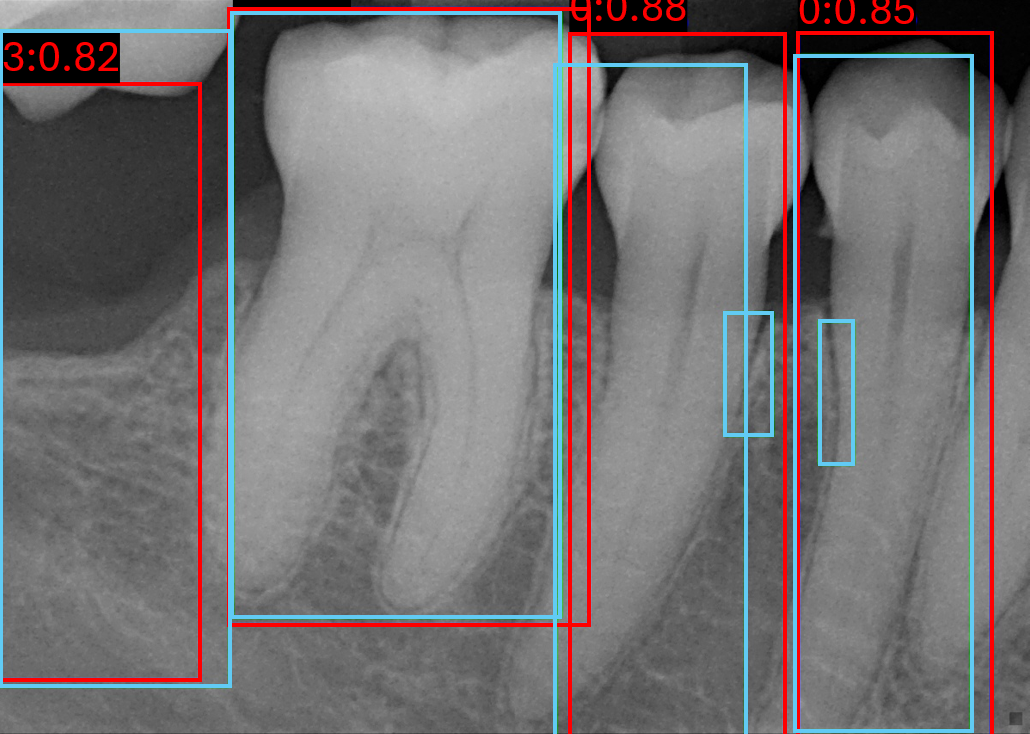

Figure 7 shows qualitative examples of detection performance on the validation set. Both models generally localise tooth boundaries with high precision, although analysing RTMDet performance indicates occasionally grouping of multiple teeth within a single bounding box, while still often retaining the appropriate number of boxes per tooth in the image. In some cases, both methods detect teeth absent from the annotations, suggesting improved actual sensitivity relative to the ground truth but at the cost of reduced quantitative precision.

Refer to caption

(a) Image 119 YOLOv8

(b) Image 120 YOLOv8

(c) Image 171 YOLOv8

(d) Image 119 RTMDet

(e) Image 120 RTMDet

(f) Image 171 RTMDet

Figure 7: Six validation images with overlaid bounding box results, where light blue is the target boxes and red is the predicted boxes.

Both models consistently fail on PLS classes, despite its higher sample size compared to ARR and triple root classes, shown in Figure 7(b) and Figure 7(e). This limitation is likely due to the visual similarity between healthy and widened PLS cases, indicative of a more challenging detection problem. In contrast, ARR and triple root teeth exhibit richer and more distinctive features, leading to stronger performance overall. However, false negative predictions for ARR remain evident throughout, in Figure 7(c) and Figure 7(f).